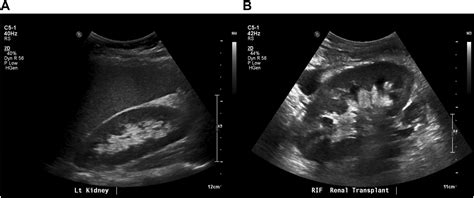

A kidney ultrasound, or sonography, uses high-frequency sound waves to create images of the kidneys, ureters, and bladder. It is frequently the first line of investigation for clinicians because it is safe, widely available, and highly effective at identifying structural abnormalities. When a radiologist reviews the images, they are looking for specific markers that indicate health versus disease.

When you receive a report stating you have a Normal Ultrasound Of Kidneys, it means that the radiologist has evaluated several specific parameters and found them to be within expected clinical ranges. The kidneys are evaluated for their size, shape, position, and internal architecture. If these elements match the standard anatomical profile for a healthy adult, the organ is considered functioning structurally as intended.

The term Normal Ultrasound Of Kidneys is standardized by medical imaging professionals. During the procedure, the sonographer maneuvers a transducer over your abdomen and back, capturing images from multiple angles. The following table summarizes what clinicians identify as normal characteristics compared to potential abnormal findings.

The test is also used for patients with a history of kidney disease to monitor the progression of conditions over time. By comparing current images to past scans, doctors can observe if the kidneys are maintaining their size and structural integrity, which is vital for managing long-term renal health.

After the radiologist interprets the images, they issue a report. If the report highlights a Normal Ultrasound Of Kidneys, it is a significant indicator that there are no major obstructive or structural pathologies present at that moment. However, medical results should always be contextualized. For example, some people have anatomical variations, such as a "horseshoe kidney" or a duplex collecting system, which are congenital differences that are not necessarily "diseased" but are considered variations of normal.

• normal vs abnormal kidney ultrasound